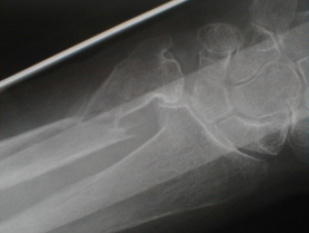

右前腕骨骨折

整復固定後再転位

再整復固定